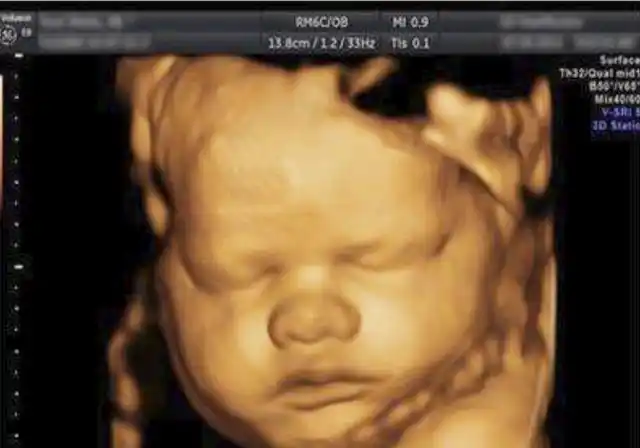

四维归来,高鼻梁大额头健康宝宝一枚

胎儿四维照鼻梁塌陷宝爸质疑妈妈基因伪劣出生后却很惊喜

怀孕6个月宝宝四维拍照嘴巴和鼻子都好大生出来后是不是很丑

大家好,帮忙看看宝宝的两次四维照,鼻子是不是好大好塌好短啊,生出来

宝宝前两天照的四维,鼻子那块挡住东西了,医生说显像问题,可是谁能